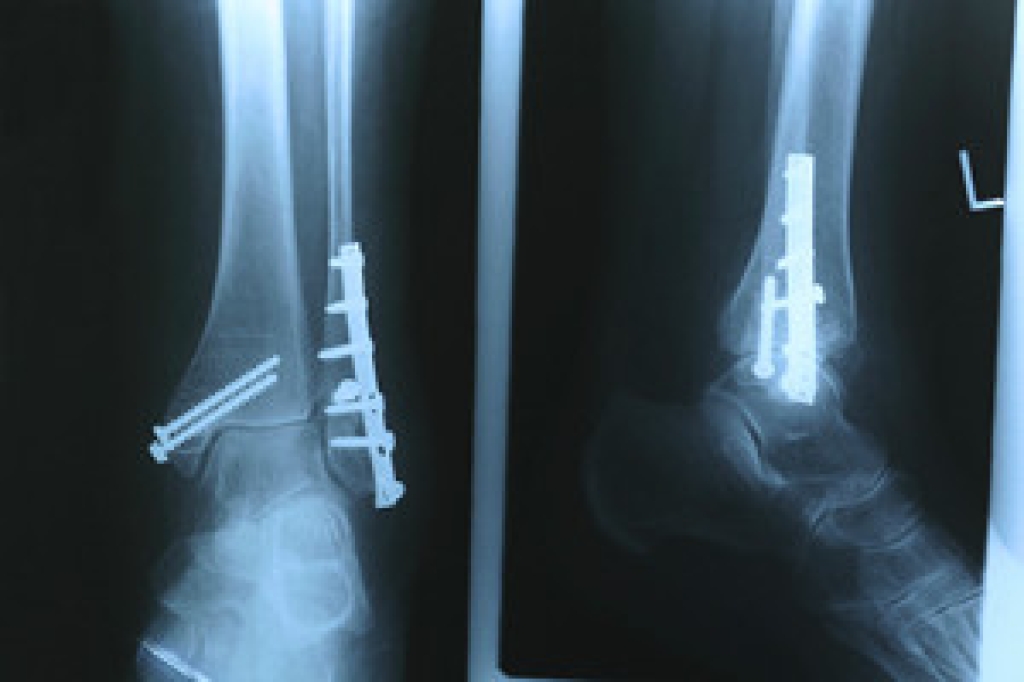

Ankle fracture surgery is performed to treat severe fractures that cannot be healed through non-surgical methods. This type of surgery is often required when bones are displaced, or the fracture is unstable, making it difficult for the ankle to heal properly. During the procedure, the surgeon realigns the broken bones and uses screws, plates, or rods to hold them in place while they heal. Ankle fracture surgery is typically followed by a period of immobilization, often involving a cast or brace to protect the ankle. Rehabilitation, which often includes specific stretches and exercises, is essential to restore strength, flexibility, and range of motion. While complications are rare, they can include infection, nerve damage, or problems with bone healing. If you have fractured your ankle, it is suggested that you consult a podiatrist who can determine what the best treatment is for you, which may include surgery.